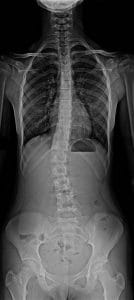

Un espinograma es un estudio radiográfico especial que permite obtener una visión panorámica completa de toda la columna vertebral, desde la base del cráneo hasta la pelvis, en una sola imagen. A diferencia de las radiografías convencionales, que suelen enfocarse solo en un segmento (como la columna cervical o dorsal), el espinograma captura la relación entre todas las piezas del rompecabezas óseo, permitiendo evaluar cómo se compensan unas con otras.

El procedimiento es sencillo, rápido y no invasivo. El paciente debe permanecer de pie (en bipedestación) frente al equipo de rayos X. Es crucial que el estudio se realice con el paciente soportando su propio peso, ya que esto revela cómo se comporta la columna bajo la fuerza de la gravedad. Generalmente, se toman dos placas: una de frente (anteroposterior) y otra de perfil (lateral), para obtener una visión tridimensional de la alineación.

La principal función de este estudio es evaluar la alineación vertebral. En una visión de frente, la columna debe presentarse perfectamente recta desde arriba hacia abajo. Los médicos suelen compararlo con la «plomada de un albañil»: si trazamos una línea vertical desde el centro del cuello, esta debe caer exactamente en medio de la pelvis. Cualquier desviación lateral de esta línea podría indicar la presencia de una escoliosis.

En la visión de perfil, el espinograma nos permite analizar las curvaturas naturales que debe tener una espalda sana. La columna no es recta de lado, sino que presenta curvas que actúan como resortes para amortiguar impactos. Estas son la lordosis (concavidad hacia atrás) en las zonas cervical y lumbar, y la cifosis (curvatura hacia adelante) en las zonas dorsal y sacra. El equilibrio entre estas curvas es lo que nos permite mantener una postura erguida sin esfuerzo excesivo.

El espinograma es pedido frecuentemente para pacientes con sospecha de escoliosis, especialmente en adolescentes durante su etapa de crecimiento. Al ser una placa única, permite medir el «ángulo de Cobb», que determina la gravedad de la curva lateral y ayuda a decidir si es necesario el uso de corsé o, en casos severos, una cirugía de corrección.